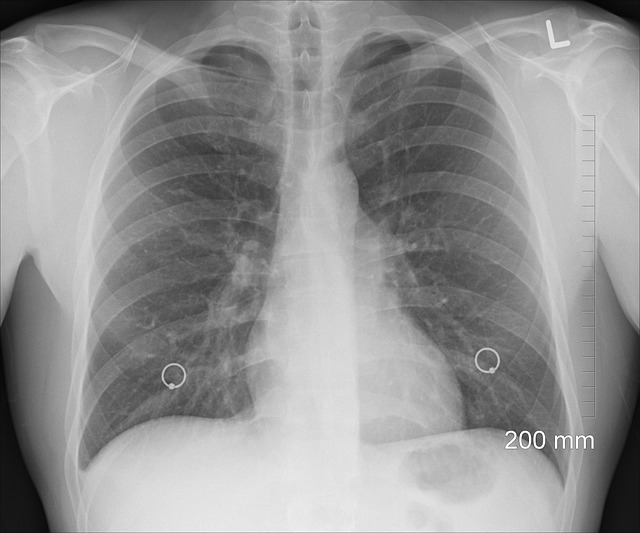

Popcorn lung is an irreversible disease that narrows and scars the small airways in your lungs. This is followed by a chronic cough, shortness of breath, and wheezing. These symptoms typically persist even after treatment, and a transplant or oxygen therapy is often required in severe cases. According to medical centers, diacetyl is considered safe to consume, but it can be potentially dangerous if inhaled. This issue first came to public light in the early 2000s, after health officials started investigating cases of severe lung disease among workers at a microwave popcorn manufacturing facility in Missouri. The investigation found that the likely suspect was diacetyl, which was being inhaled at the microwave popcorn plant. These findings led to changes in occupational recommendations and industry practices.